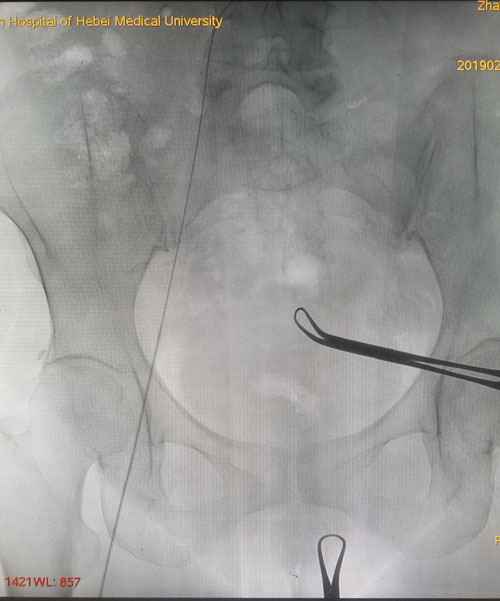

术前CTV评估股静脉及分支

术中DSA评估导丝走形